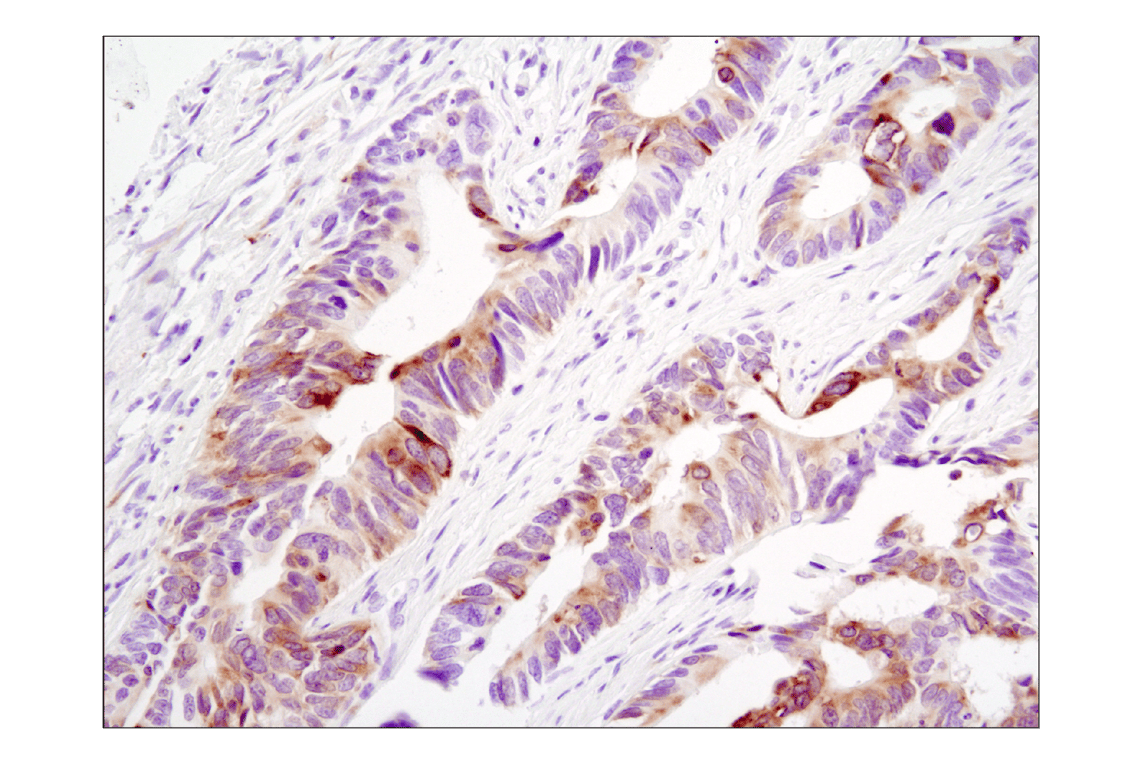

Immunohistochemical analysis of paraffin-embedded human colon carcinoma using Phospho-S6 Ribosomal Protein (Ser235/236) (D57.2.2E) XP® Rabbit mAb.

Immunohistochemistry Image 3: Phospho-S6 Ribosomal Protein (Ser235/236) (D57.2.2E) Rabbit Monoclonal Antibody